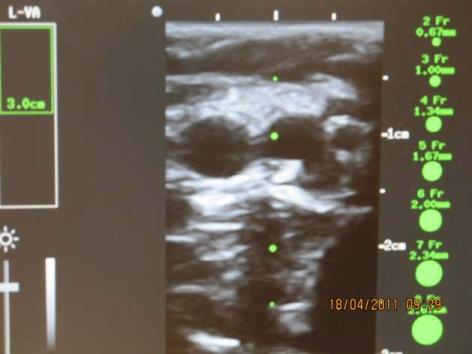

Prezentujeme výhody zavedení periferní cestou implantované centrální kanyly (PICC) coby permanentního žilního vstupu u pacientů s nádory hlavy a krku a srovnání s ostatními možnostmi zajištění žilního vstupu. PICC je zaveden za přímé ultrazvukové navigace s užitím sterilního návleku cestou jedné z žil v oblasti mediální strany paže v.basilica, v.brachialis nebo v.cephalica (obr. 1,2,3).

Obr. 1 Znázornění punkce za ultrazvukové navigace

Obr. 2 Punkce s užitím sterilního návleku na ulztrazvukové sondě

Obr. 3 Obvyklý ultrazvukový obraz žil v oblasti mediální strany paže